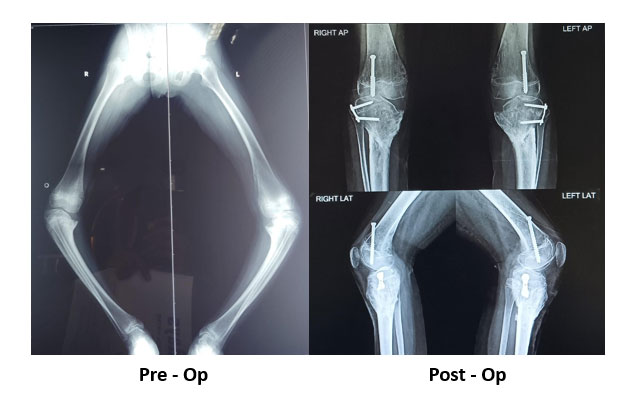

Blounts

Before Surgery

After Surgery